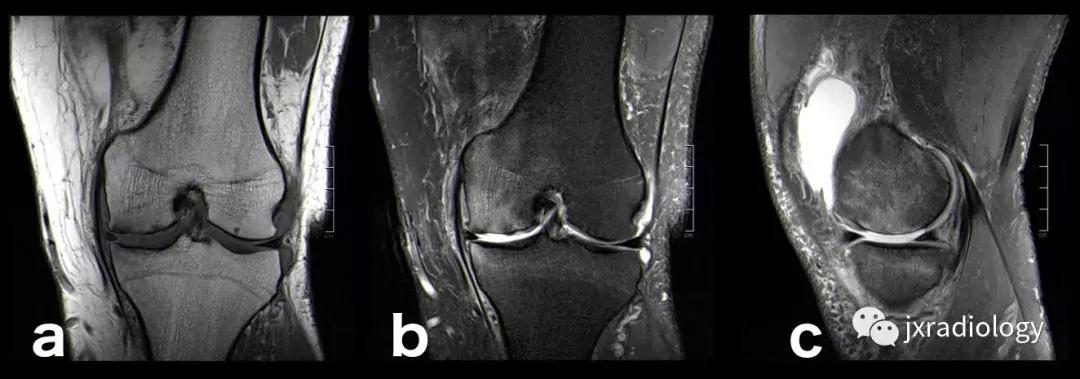

图2:骨性关节炎(OA):男,58岁,股骨内侧髁负重区有软骨缺损,伴有边缘小骨赘和继发性软骨下骨髓水肿。骨性关节炎通常不与创伤性病因分类,而是作为退行性病变分类(a:冠状T1-WI; b:冠状PDWI-FS; c:矢状PDWI-FS)。